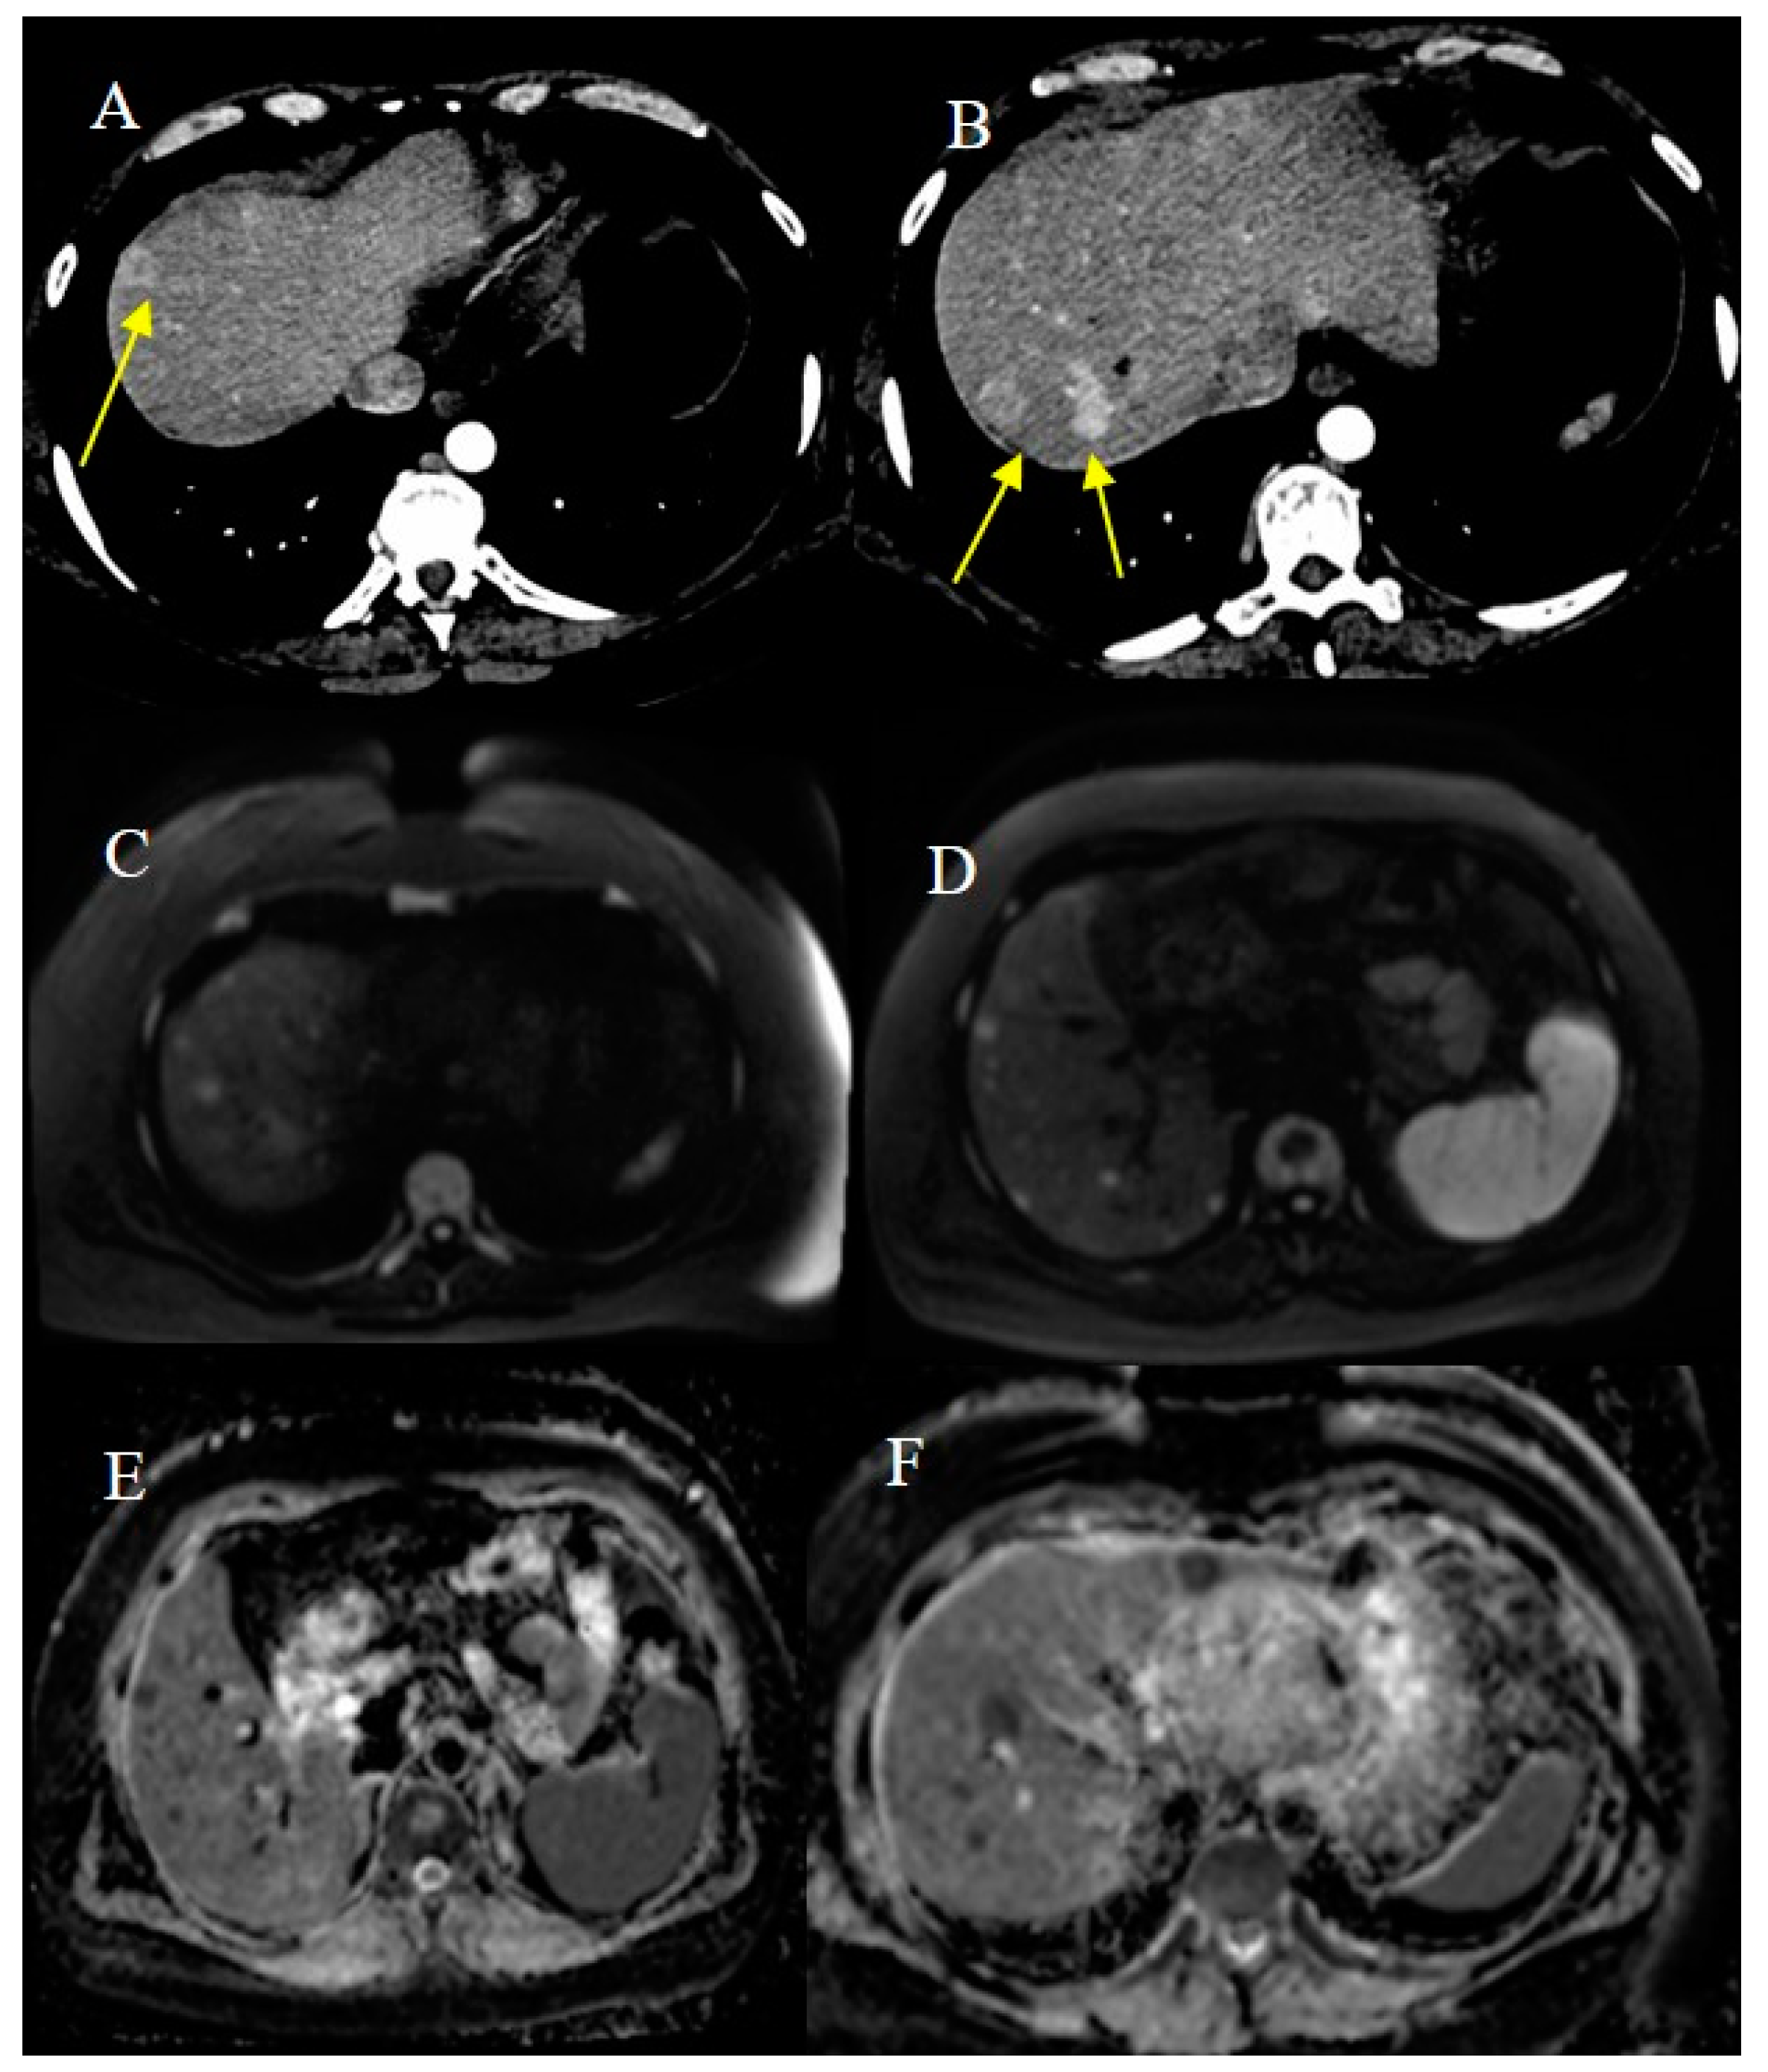

2.7. Metastatic Presentation of Small Bowel Tumors

- Attiyeh, M.A.; Malhotra, G.K.; Li, D.; Manoukian, S.B.; Motarjem, P.M.; Singh, G. Defining MRI Superiority over CT for Colorectal and Neuroendocrine Liver Metastases. Cancers 2023, 15, 5109. [Google Scholar] [CrossRef]

- Shenoy-Bhangle, A.; Baliyan, V.; Kordbacheh, H.; Guimaraes, A.R.; Kambadakone, A. Diffusion weighted magnetic resonance imaging of liver: Principles, clinical applications and recent updates. World J. Hepatol. 2017, 9, 1081. [Google Scholar] [CrossRef]